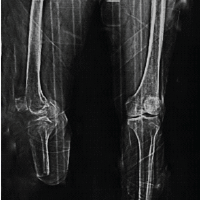

A middle-aged male in his fifties presented to our institution with a 3-year history of persistent right-sided neck and shoulder pain. The pain, localized to the posterior neck and right supraclavicular region, had been managed symptomatically at multiple local healthcare facilities without definitive relief. There was no radiation of pain or paraesthesia in either upper limb. The patient had previously been treated for cervical spondylosis, with partial symptom relief following analgesics; however, the symptoms persisted. On detailed history, the patient reported having undergone surgical fixation for a right shoulder fracture 6 years prior (Fig. 1a).

Figure 1: Old radiograph of the right shoulder showing tension band wiring of the acromioclavicular joint and a malunited but healed lateral end clavicle fracture (a); Recent radiograph of the right shoulder (b) and neck demonstrating two broken K-wire fragments migrated to the posterior neck on the right side-one located in the right supraclavicular region and the other at the posterior aspect of the neck (c).

Clinical examination revealed no signs of radiculopathy, motor weakness, or restriction in neck mobility. However, a palpable small swelling (3 × 2 cm) was noted in the right supraclavicular region. The carotid artery was well palpated, and the swelling was lateral to the vascular bundle. Radiographs of the shoulder and neck revealed two broken K-wire fragments – one located in the right supraclavicular region and another posteriorly near the cervical spine (Fig. 1b and c). The shoulder radiograph showed a malunited lateral end clavicle fracture fixed with tension band wiring over two K-wires, both of which were broken distally. A non-contrast computed tomography (CT) scan of the neck was performed to delineate the exact position of the migrated wires (Fig. 2). The case was reviewed in a multidisciplinary team setting with input from an otorhinolaryngology expert. Routine pre-operative laboratory investigations were within normal limits, and the patient was planned for elective hardware removal.